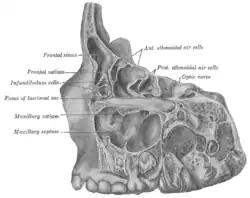

Specimen from a child eight years, eight months, and one day old. Lateral view of frontal, ethmoidal and maxillary sinus areas, the lateral portion of each having been removed by sagittal cuts. ("Maxillary septa" labeled at center left.) | |